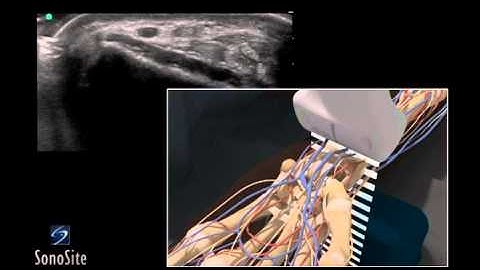

Radial Artery Access using Ultrasound